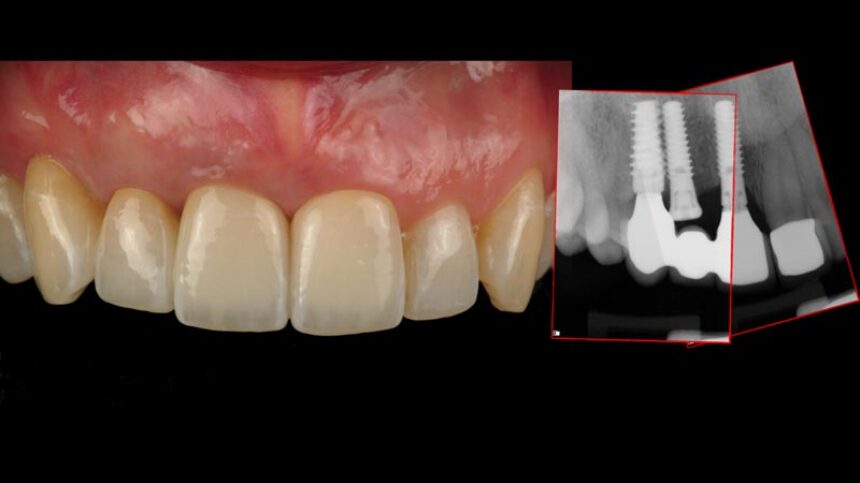

Διάγνωση, πρόληψη και αντιμετώπιση της περι-εμφυτευματίτιδας

Διαχείριση των αποτυχιών των εμφυτευμάτων στην αισθητική περιοχή, οι εναλλακτικές.